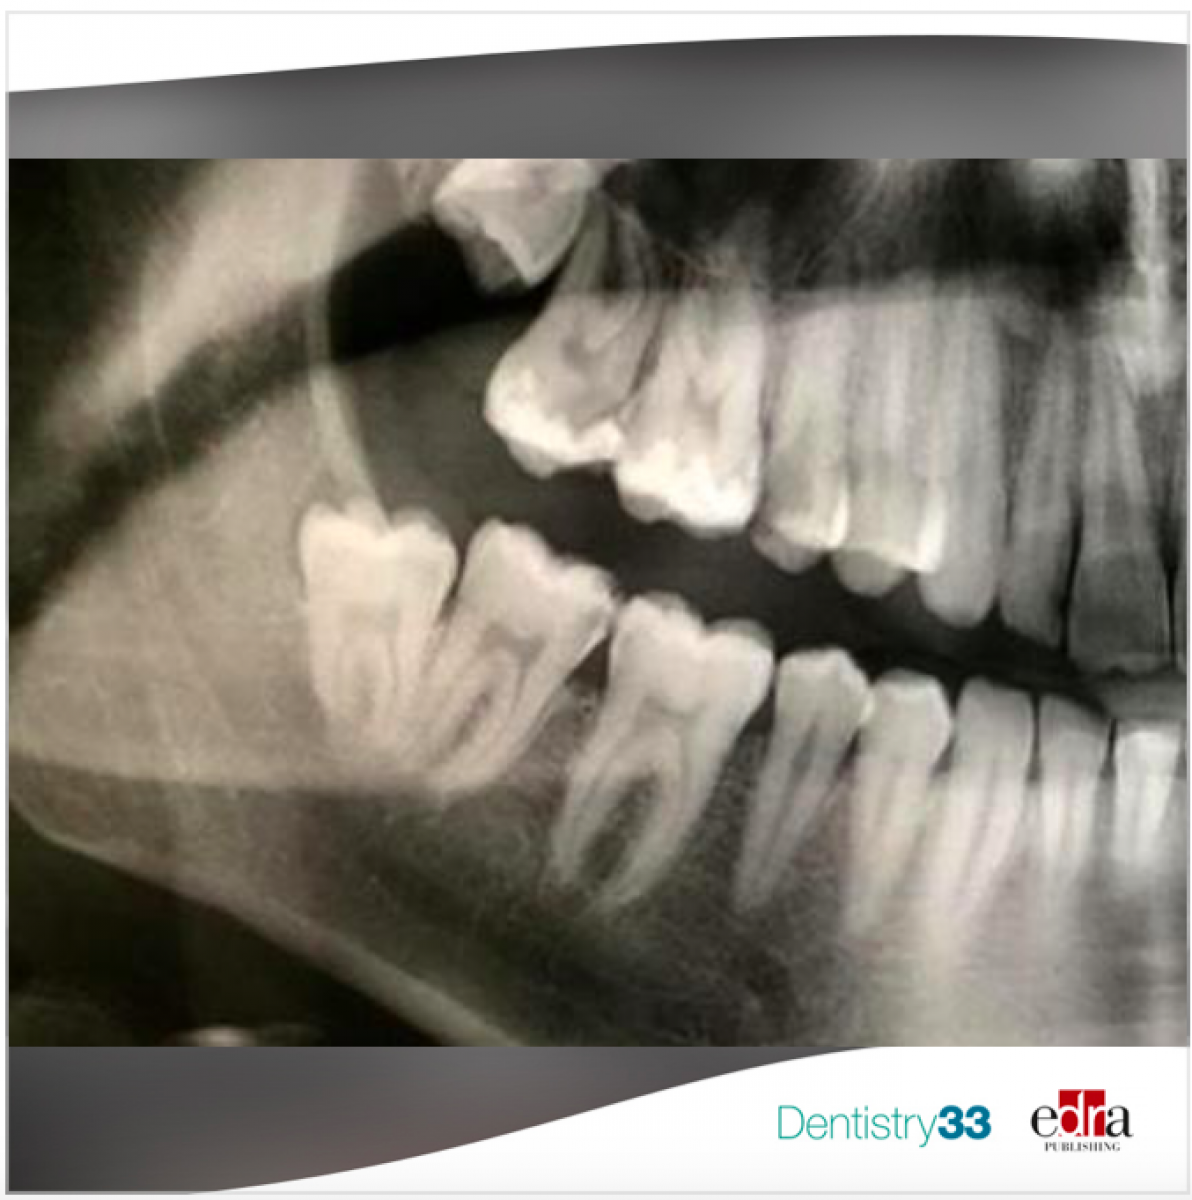

Dry socket is a common complications that develops after the extraction of a permanent tooth, and it is characterized by pain in and around the extraction site with a partial or total loss of a blood clot within the alveolar socket. It can occur in 3–4% of cases but this value may be extended to 45% with impacted tooth. The etiology of dry socket is multifactorial, but not completely clear. Density of the bone, vasoconstriction of the anesthetic agents, systemic conditions, smoking and difficulties related to the extraction are some of the conditions predisposing to dry socket. Treatment choices are multiple but due to the condition of severe pain, prevention of dry socket is of primary importance. Different modalities have been investigated in attemp to prevent the incidence.

Proper implant treatment planning remains the first priority for implant success. Dental imaging is an important tool to accomplish this task.